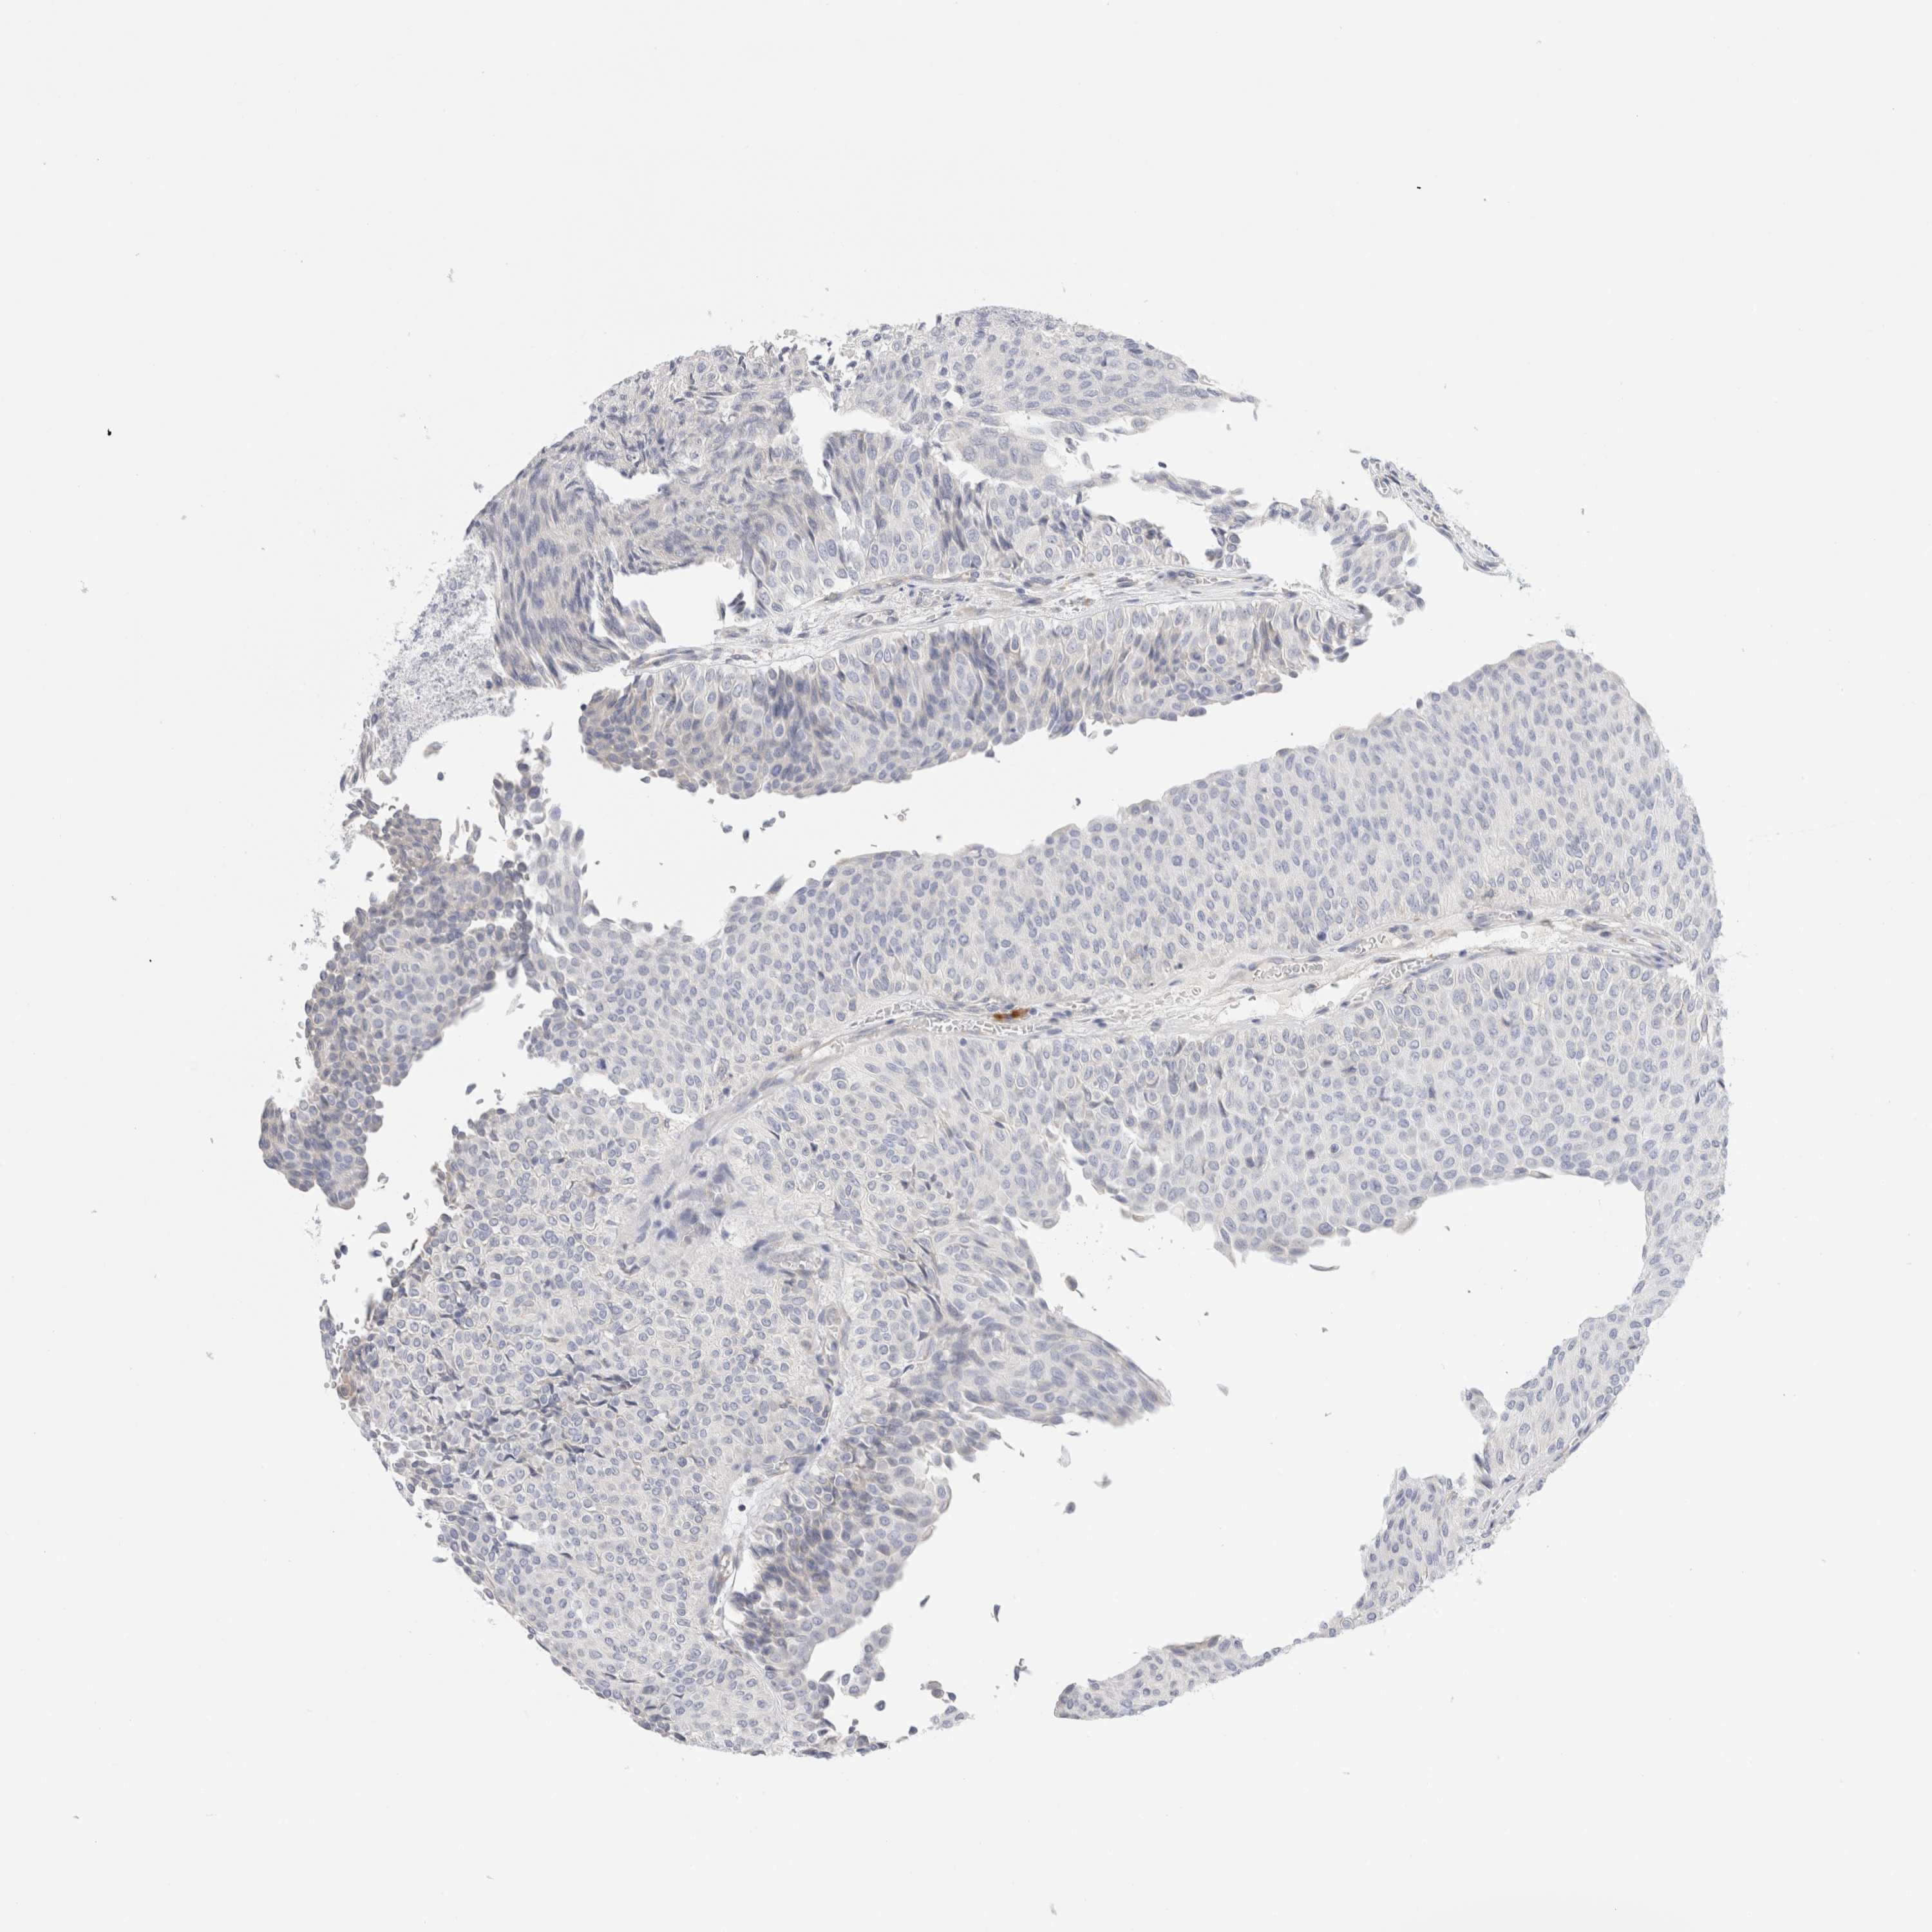

UROTHELIAL CANCER - Protein expressioni

A mouse-over function shows sample information and annotation data. Click on an image to view it in a full screen mode. Samples can be filtered based on level of antibody staining by selecting one or several of the following categories: high, medium, low and not detected. The assay and annotation is described here.

Note that samples used for immunohistochemistry by the Human Protein Atlas do not correspond to samples in the TCGA dataset.

Antibody stainingi

Antibody staining in the annotated cell types in the current human tissue is reported as not detected, low, medium, or high, based on conventional immunohistochemistry profiling in selected tissues. This score is based on the combination of the staining intensity and fraction of stained cells.

Each image is clickable and will lead to virtual microscopy that enables deeper exploration of all samples and also displays staining intensity scores, fraction scores and subcellular localization as well as patient and tissue information for each sample.

Antibody HPA026488

Antibody HPA028425

Antibody CAB011203

Staining

High

Medium

Low

Not detected

Intensity

Strong

Moderate

Weak

Negative

Quantity

>75%

75%-25%

<25%

None

Location

Nuclear

Cytoplasmic/membranous

Cytoplasmic/membranous,nuclear

Urothelial carcinoma, Low grade

Urothelial carcinoma, High grade